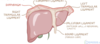

How many main lobes does the liver have?

- 2

- left and right (right is bigger)

What are the superior and inferior borders or the liver called?

- superior = diaphragmatic surface

- inferior = visceral surface

What are the 2 accessory lobes of the liver called?

1 - quadrate

2 - caudate

What is the large white struction on the anterior section of the liver and what role does it have in providing stability to the livers anatomical position?

- falciform

- attaches liver to anterior wall of abdomianl cavity

What is the hilum of the liver called?

- porta hepatis

What passes through the hilium of the liver called the portal hepatis?

- portal vein

- hepatic artery proper

- common hepatic duct

- nerves and lymphatics